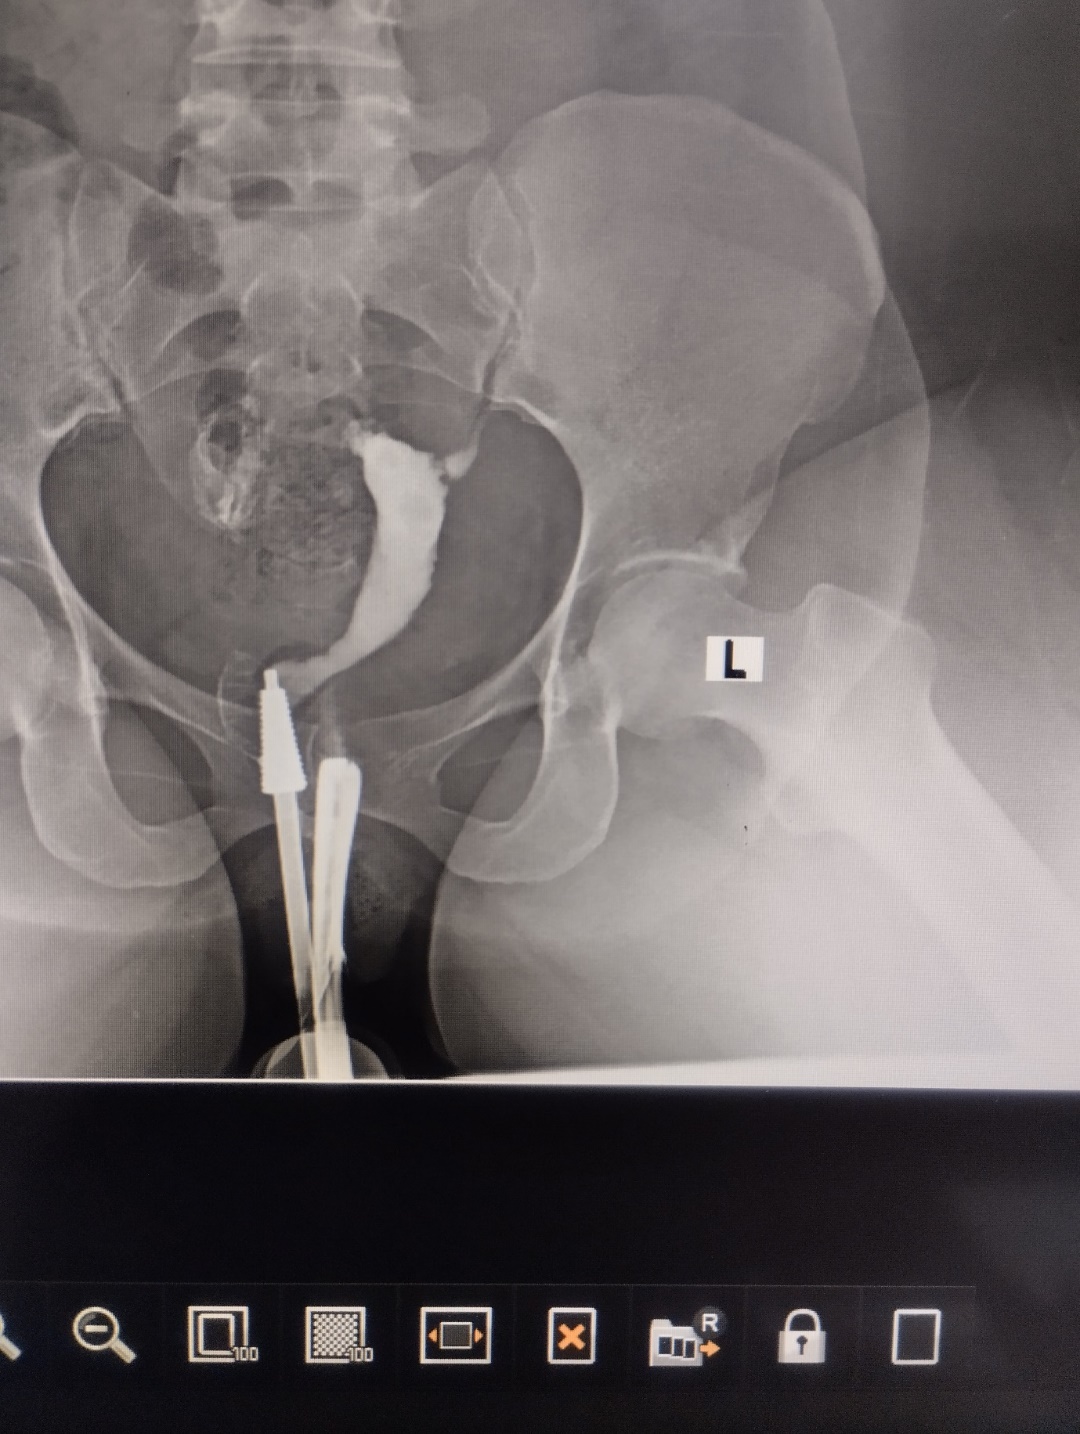

Figure 1: shows normal HSG with bilateral patent fallopian tubes

One hundred and twenty-five (41.7%) patients had normal HSG findings; this indicates that there was no structural abnormality detected in the cervical canal, uterine cavity and both fallopian tubes. This finding is consistent with a study in Sokoto, North-West Nigeria, which reported a comparable prevalence of normal findings15. However, it is higher than the findings recorded in Maiduguri, North-Eastern Nigeria16 and Korle-Bu, Ghana14. The relatively higher prevalence of normal findings in this study might be attributed to the therapeutic effects of the HSG procedure, which is known to resolve certain mild tubal blockages, resulting in normal imaging appearances14.